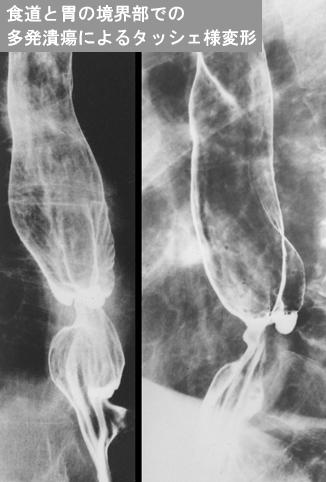

Posted by: Tokyo Pref., Cooperative study between National Cancer Center and Kyushu Cancer Center

ID:12206